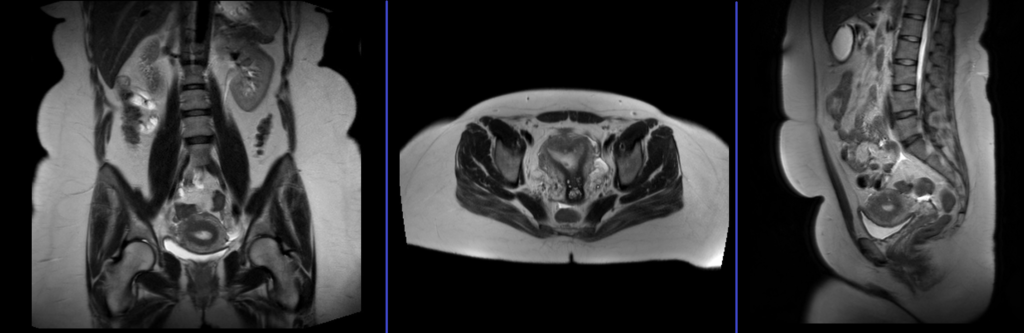

Endometrial MRI scans localiser

A three plane localiser must be taken in the beginning to localise and plan the sequences. Localisers are normally less than 25sec. T1 weighted low resolution scans.